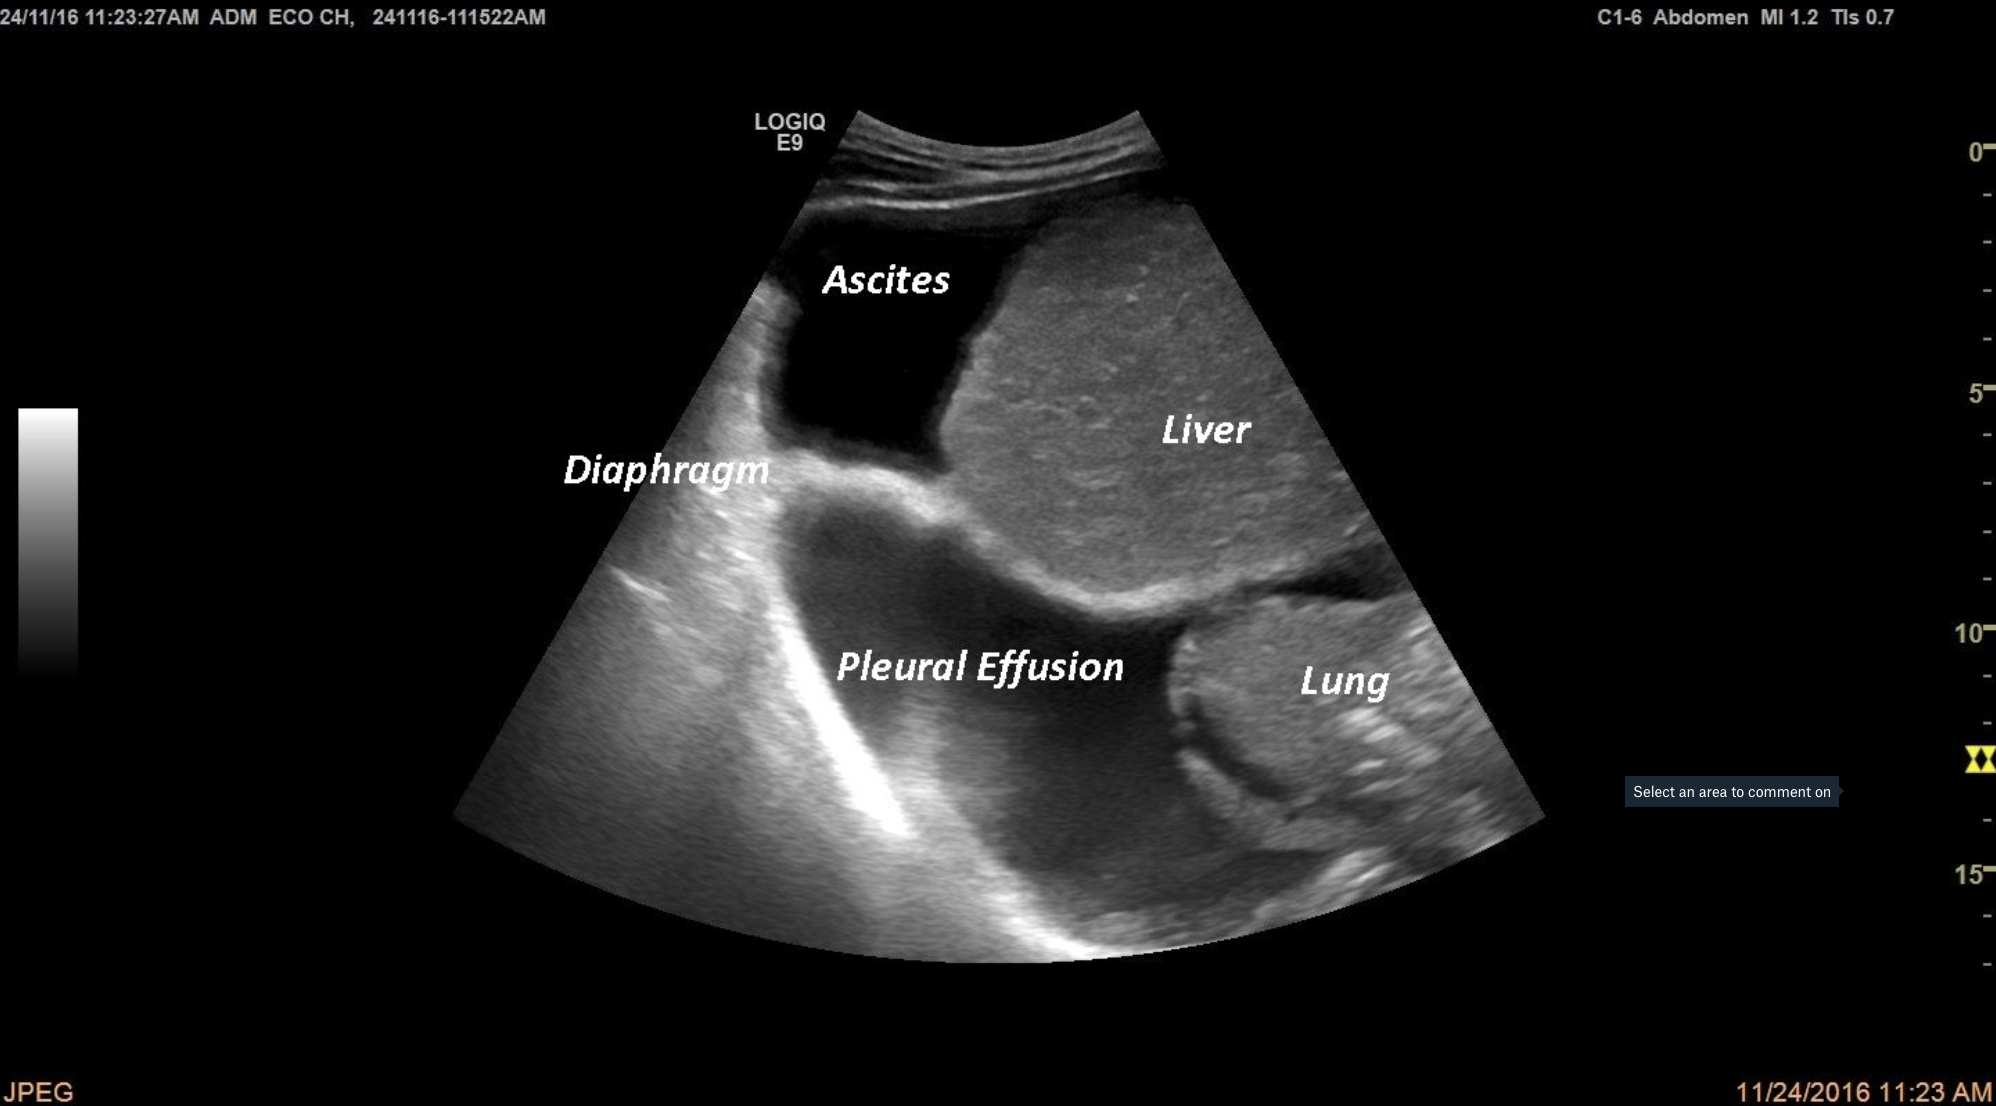

TITLE: Ascites and Pleural Effusion in a cirrhotic patient

A patient with a history of decompensated liver cirrhosis presented himself into the emergency room for dyspnea and abdominal distension. At standard ultrasound we can see fluid (anechoic structure) inside the abdomen (ascites)and inside the thorax (pleural effusion).

Ascites, Pleural effusion, liver cirrhosis